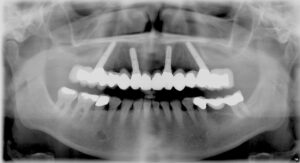

Früher galt die Regel, dass nur mit 6-8 Implantate eine stabile Abstützung für feste Zähne bei Zahnlosigkeit möglich ist. Das All-on-four-Konzept® der Firma NobelBiocare widerlegt diese These: auch mit 4 Zahnimplantaten ist es sicher, einen zahnlosen Kiefer mit festen Zähnen zu versorgen. Die 4 Implantate beim All-on-4-Konzept® nutzen das meist noch günstige Knochenangebot in vorderen Kieferabschnitt. 2 Implantate sitzen im Frontbereich, die beiden anderen Implantate werden weiter hinten schräg platziert, mit der Implantatspitze nach vorne gerichtet. Dadurch wird das Knochenangebot unterhalb der Kieferhöhle im Oberkiefer und über dem Hauptnerv im Unterkiefer voll ausgenutzt. Verletzungen des Nerven oder ein Knochenaufbau unterhalb der Kieferhöhle (Sinuslift) werden so vermieden.

Feste Brücke auf 4 Implantaten: hintere Implantate schräg eingebracht: stabil!

Auch im zahnlosen Unterkiefer ist der Knochenabbau (Atrophie) im Seitenzahnbereich ausgeprägter als in der Frontregion. Hier ist der Grenzpunkt meist der Austrittspunkt des Kinn-Nerven in Höhe des 5. Zahnes. Die hinteren Implantate werden so schräg eingebracht (siehe Bild oben) dass Implantatkopf hinter und die Implantatspitze vor dem Nerven liegt.